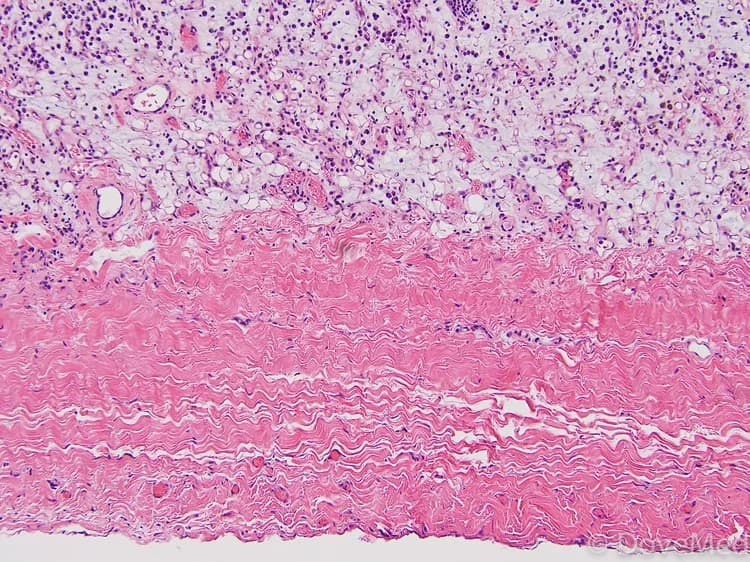

• Pericarditis refers to swelling and inflammation of the pericardium, a sac-like layer that covers the heart. The pericardium contains a fluid that keeps the heart muscle moist and ensures a smooth function

• Generally, this sac becomes inflamed due to an underlying infection that results in friction between the membrane and muscle causes a stabbing chest pain, thereby leading to pericarditis. However, in some cases, pericarditis may be caused by non-infectious agents or underlying disorders